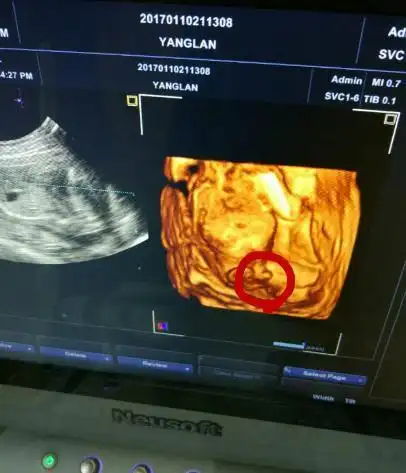

怀孕四个月宝宝在子宫内做些什么胎宝说妈妈你猜猜吧

四维照到明显小jj 男宝果然好调皮 附男宝症状

四个月的时候可以看到男孩的睾丸下降

四维彩超看到的胎儿生理结构图